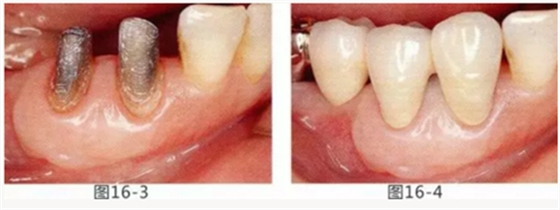

圖16-1 右3,4牙周袋探診值為3~4mm,基本沒有附著齦。右下3部位的系帶也附著在牙頸部附近,由于清潔困難而引發(fā)了炎癥。

圖16-2 由于磨牙部缺失,為了能夠進行固定修復而在右下6位置植入種植體,制作右下3,4,5,6固定橋冠。為了增加基牙右下3,4周圍的附著齦,在實施FGG同時去除系帶。

圖16-3 獲得了足夠附著齦,可以抵抗刷牙等外部刺激。

圖16-4 獲得充分附著齦,易清潔的狀態(tài)。修復體之間的鼓形間隙大小均一也使清潔性得到提升。

圖16-5 佩戴最終修復體3年后的狀態(tài)。

圖16-6 佩戴最終修復體11年后的狀態(tài)。無牙齦萎縮保持著安定狀態(tài)。

圖16-7 配戴最終修復體18年后的狀態(tài)。